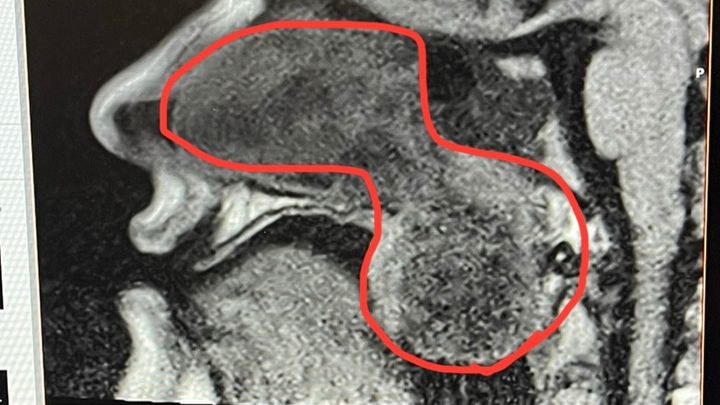

Alright, it's time for Round 2 of Sinus Surgery! Why didn't it work the first time, you may ask? Because the doctors I was with misdiagnosed me and made my problems WORSE! The nasal polyps I had came back in full force, and for the past few months, I've been going through tissue box after tissue box with the amount of mucus I seem to be producing. So now, not only can I not breathe out of my nose, but my nose is also always leaking! Not only that, but the polyps have gotten to the point where they're hanging in the back of my throat and impacting my breathing and speech. SO, all this to say, I need to get the surgery again so my new doctor can begin treating the root cause. Anything helps, whether it's a donation or just sharing this, but after my latest CT scan, my doctor is trying to get the surgery as soon as possible because of the effects it's having on my body.

TLDR: First doctors misdiagnosed me, so now I'm worse than before and have to do it all again. Also now, this doctor is in a hurry cause it's baaaaaad.